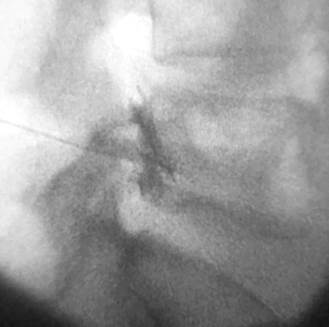

Al no responder al tratamiento instituido en base a tramadol y ketoprofeno, se le realizó una inyección peridural transforaminal de corticoides a nivel de los forámenes L4 y L5 derechos, (Figuras 1 y 2) según guía de la SIS (Spinal Injection Society). Previo control con 1 ml. de contraste iodado (iopamidol 300 mg/ml), se le administraron 20 mg de triamcinolona + 1 ml lidocaína 0.5% en cada foramen. Aproximadamente 6 horas después del procedimiento, instaló episodios de hipo de 8-10 por minuto, de 2 o 3 horas de duración, que se repitieron por un período de 50 horas, con interferencia en el descanso y en la alimentación. Los tradicionales tratamientos no farmacológicos tales como tragar agua fría, mantener la respiración, respirar en una bolsa, o la aplicación de masaje carotideo o presión supraorbital resultaron inefectivos, por lo que se le administró inicialmente 10 mg de domperidona intravenosa (iv) c/8 horas en las primeras 24 horas.